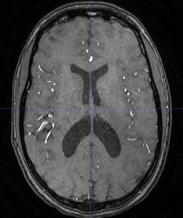

The use of deep learning techniques for 3D brain vessel image segmentation has not been as widespread as for the segmentation of other organs and tissues. This can be explained by two factors. First, deep learning techniques tend to show poor performances at the segmentation of relatively small objects compared to the size of the full image. Second, due to the complexity of vascular trees and the small size of vessels, it is challenging to obtain the amount of annotated training data typically needed by deep learning methods. To address these problems, we propose a novel annotation-efficient deep learning vessel segmentation framework. The framework avoids pixel-wise annotations, only requiring patch-level labels to discriminate between vessel and non-vessel 2D patches in the training set, in a setup similar to the CAPTCHAs used to differentiate humans from bots in web applications. The user-provided annotations are used for two tasks: 1) to automatically generate pixel-wise labels for vessels and background in each patch, which are used to train a segmentation network, and 2) to train a classifier network. The classifier network allows to generate additional weak patch labels, further reducing the annotation burden, and it acts as a noise filter for poor quality images. We use this framework for the segmentation of the cerebrovascular tree in Time-of-Flight angiography (TOF) and Susceptibility-Weighted Images (SWI). The results show that the framework achieves state-of-the-art accuracy, while reducing the annotation time by up to 80% with respect to learning-based segmentation methods using pixel-wise labels for training